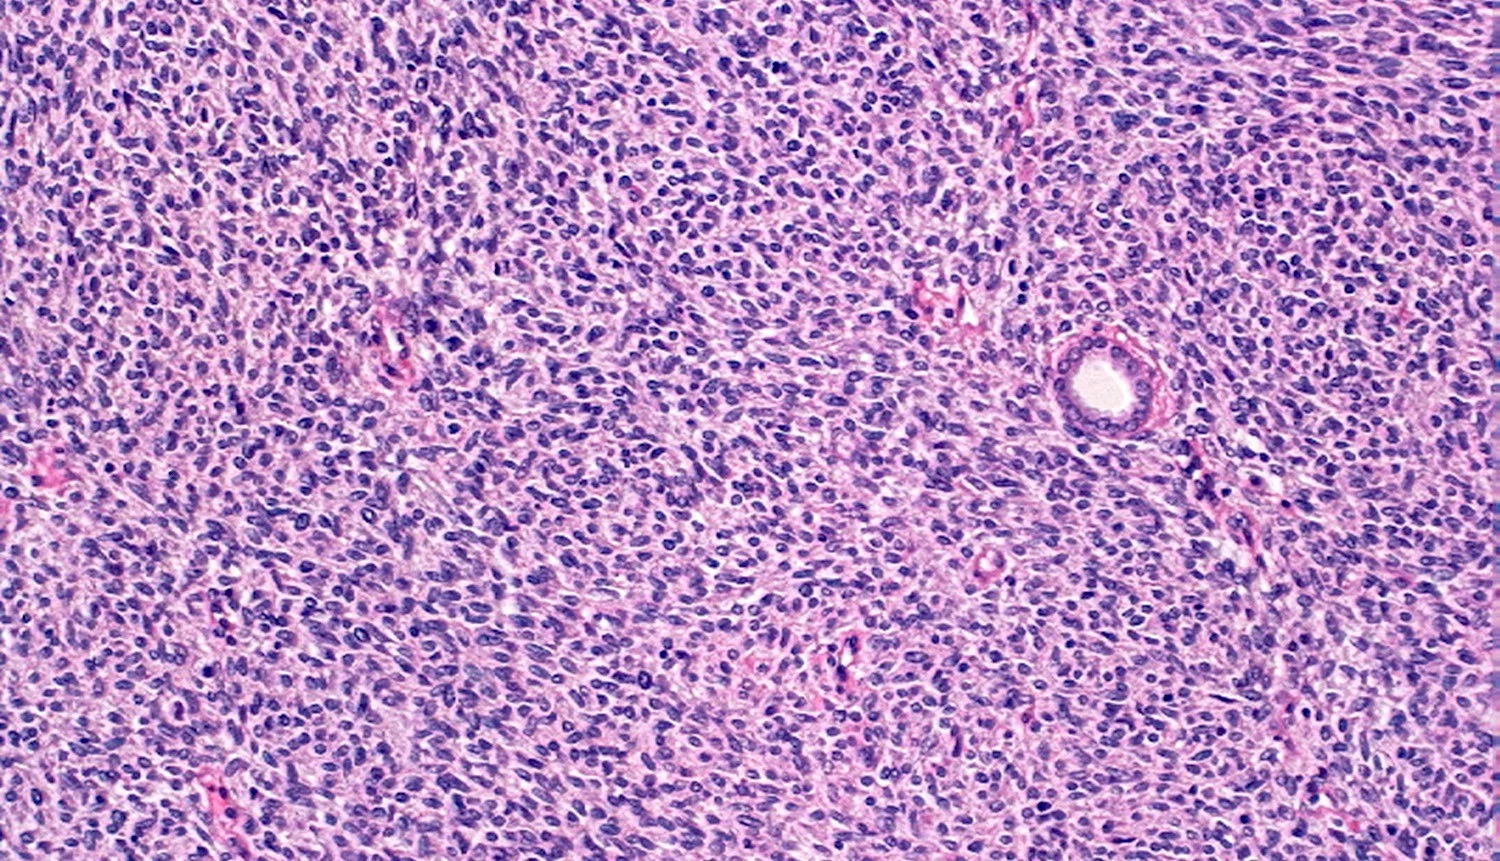

سارکوم سلول شفاف کلیه (Clear cell sarcoma of kidney یا CCSK)

این تومورها نسبت به تومورهای ویلمز به سایر قسمت‌های بدن سرایت می‌کنند و درمان آن‌ها سخت‌تر است. از آن جایی که این تومورها نادر هستند، درمان اغلب به عنوان بخشی از یک کار آزمایی بالینی انجام می‌شود. این روش معمولاً بسیار شبیه درمان فشرده مورد استفاده برای تومورهای ویلمز با بافت شناسی آناپلاستیک است (به مبحث درمان تومورهای ویلمز بر اساس نوع و مرحله مراجعه کنید).